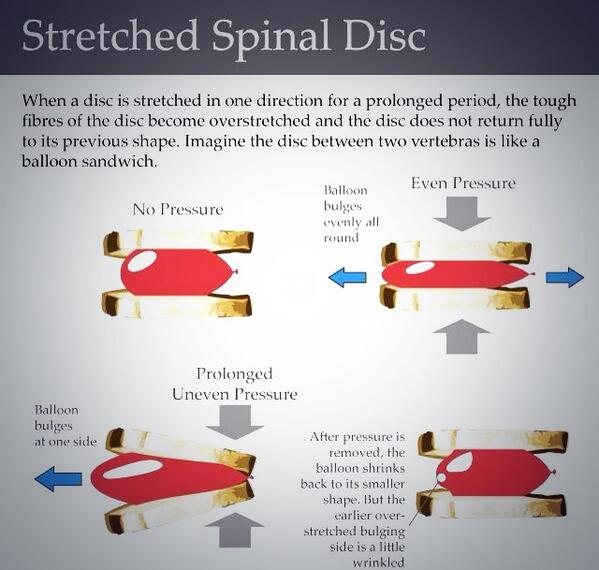

Do you know what a stretched spinal disc is? #wellness #spine #spinaldisc #chiro #chiropractor #backpain

Do you know what a stretched spinal disc is? #wellness #spine #spinaldisc #chiro #chiropractor #backpain